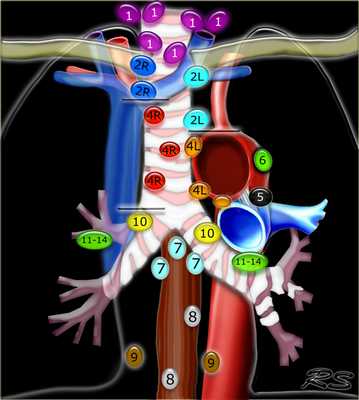

Лимфатические узлы средостения

Лимфатические узлы 3 группы не примыкают к трахее в отличии от лимфатических узлов 2 группы. Они подразделюятся на: 3А кпереди от сосудов 3Р позади пищевода/превертебрально Они не доступны при медиастиноскопии. 3Р группа может быть доступна при чреспищеводной эхокардиографии.

На изображении слева 3А узел в преваскулярном пространстве. Обратите внимание так же на ниже расположенные паратрахеальные узлы справа относящиеся к 4R группе.

4R. Правые нижние паратрахеальные лимфатические узлы

- Верхняя граница: пересечение нижнего края левой плечеголовной вены с трахеей.

- Нижняя граница: нижний края непарной вены. 4R узлы распространяются до левого края трахеи.

На изображении слева мы видим 4R паратрахеальные узлы. Кроме того здесь представлен узел кнаружи от дуги аорты, то есть 6 группы.

4L. Левые нижние паратрахеальные лимфатические узлы

4L узлы расположенные слева от левой стенки трахеи, между горизонтальными линиями проведенными касательно верхней стенке дуги аорты и линией проходящей через левый главный бронх на уровне верхнего края верхнедолевого бронха. Они включают паратрахеальные узлы расположенные кнутри от артериальной связки.

Узлы 5 группы (аортопульмонального окна) расположены кнаружи от артериальной связки.

На левом изображении над уровнем легочного ствола представлены нижние паратрахеальные узлы слева и справа, так же здесь представлены узлы 3 и 5 групп.

Изображение слева выше уровня карины. Слева от трахеи 4L узлы. Обратите внимание что они расположены между легочным стволом и аортой, но не в аортопульмональном окне, потому что они лежат медиальнее артериальной связки. Лимфатические узлы латеральнее легочного ствола относятся к 5 группе.

- 5. Субаортальные лимфатические узлы

- Субаортальное или аортопульмональное окно расположено кнаружи от артериальной связки и проксимальнее первой ветви левой легочной артерии и лежит в пределах медиастинальной плевры.

- Парааортальные лимфатические узлы лежат кпереди и кнаружи от восходящего отдела аорты и между верхним и нижним краями дуги аорты.

7. Подкаринальные лимфатические узлы

Эти лимфатические узлы расположены ниже уровня бифуркации трахеи (карины), но не относятся к нижнедолевым бронху и артерии. Справа они располагаются каудальнее нижней стенки промежуточного бронха. Слева они располагаются каудальнее верхней стенки нижнедолевого бронха. Слева лимфатический узел 7 группы справа от пищевода.

8. Параэзофагеальные лимфатические узлы

Эти лимфатические узлы ниже подкаринальных лимфатических узлов и распространяются каудальнее до диафрагмы. На изображении слева ниже уровня карины справа от пищевода обозначен лимфатический узел 8 группы.

9. лимфатические узлы легочной связки

Данные лимфатические узлы лежат в пределах легочной связки, в том числе и по ходу нижней легочной вены. Легочная связка представлена дупликатурой медиастинальной плевры охватывающей корень легкого.

10. лимфатические узлы корня легкого

Лимфатические узлы корня расположены проксимальнее долевых узлов, но дистальнее медиастинальной дупликатуры и узлов промежуточного бронха справа.

Все лимфатические узлы 10-14 групп являются N1 узлами, так как они находятся вне средостения.

1. лимфатические узлы вырезки грудины видны только на этом уровне и выше него

2. верхние паратрахеальные лимфатические узлы: ниже ключиц , справа над пересечением нижнего края левого плечеголовного ствола и трахеи, а слева над дугой аорты

3. Преваскулярные и ретротрахеальные: кпереди от сосудов (3А) и превертебральные (3Р)

4. Нижние паратрахеальные: ниже верхнего края дуги аорты до уровня главного бронха

5. Субаортальные (аортопульмональное окно): лимфатические узлы кнаружи от артериальной связки или кнаружи от аорты или левой легочной артерии.

6. Парааортальные: узлы лежащие кпереди и кнаружи от восходящего отдела аорты и дуги аорты под верхним краем дуги аорты.

7. Субкаринальные лимфатические узлы.

8. Параэзофагеальные лимфатические узлы (ниже карины).

9. Лимфатические узлы легочной связки: лежат в пределах легочной связки.